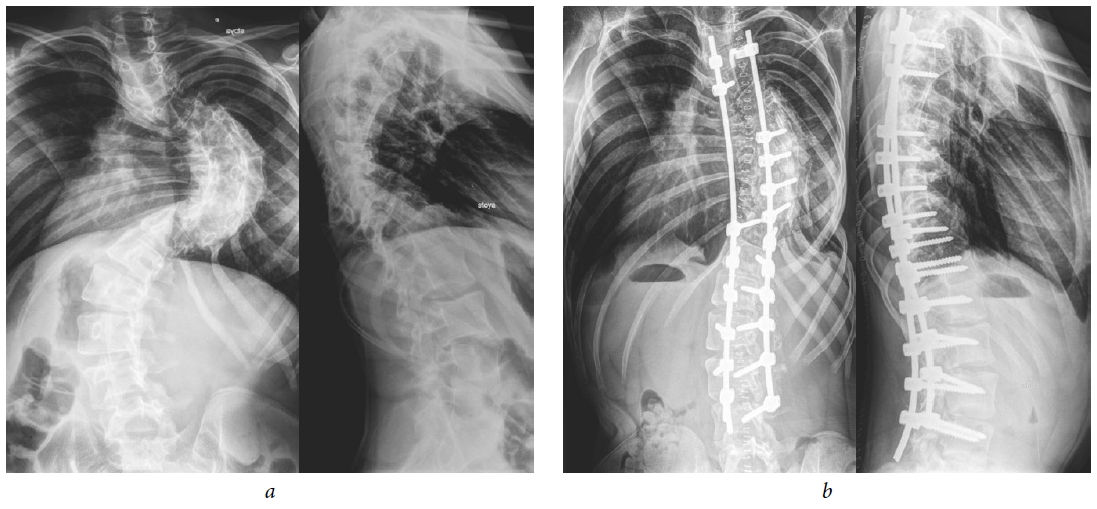

图1显示了患者S手术时的X线影像,

当时17岁,术后两年间出现特发性右侧胸椎侧弯。

图1.17岁患者S的放射片:(a)术前;(b)椎间盘切除术后,行融合术、颅骨胫骨牵引,并通过多支

撑性外科器械系统联合椎体Th7楔形切除术进行畸形矫正